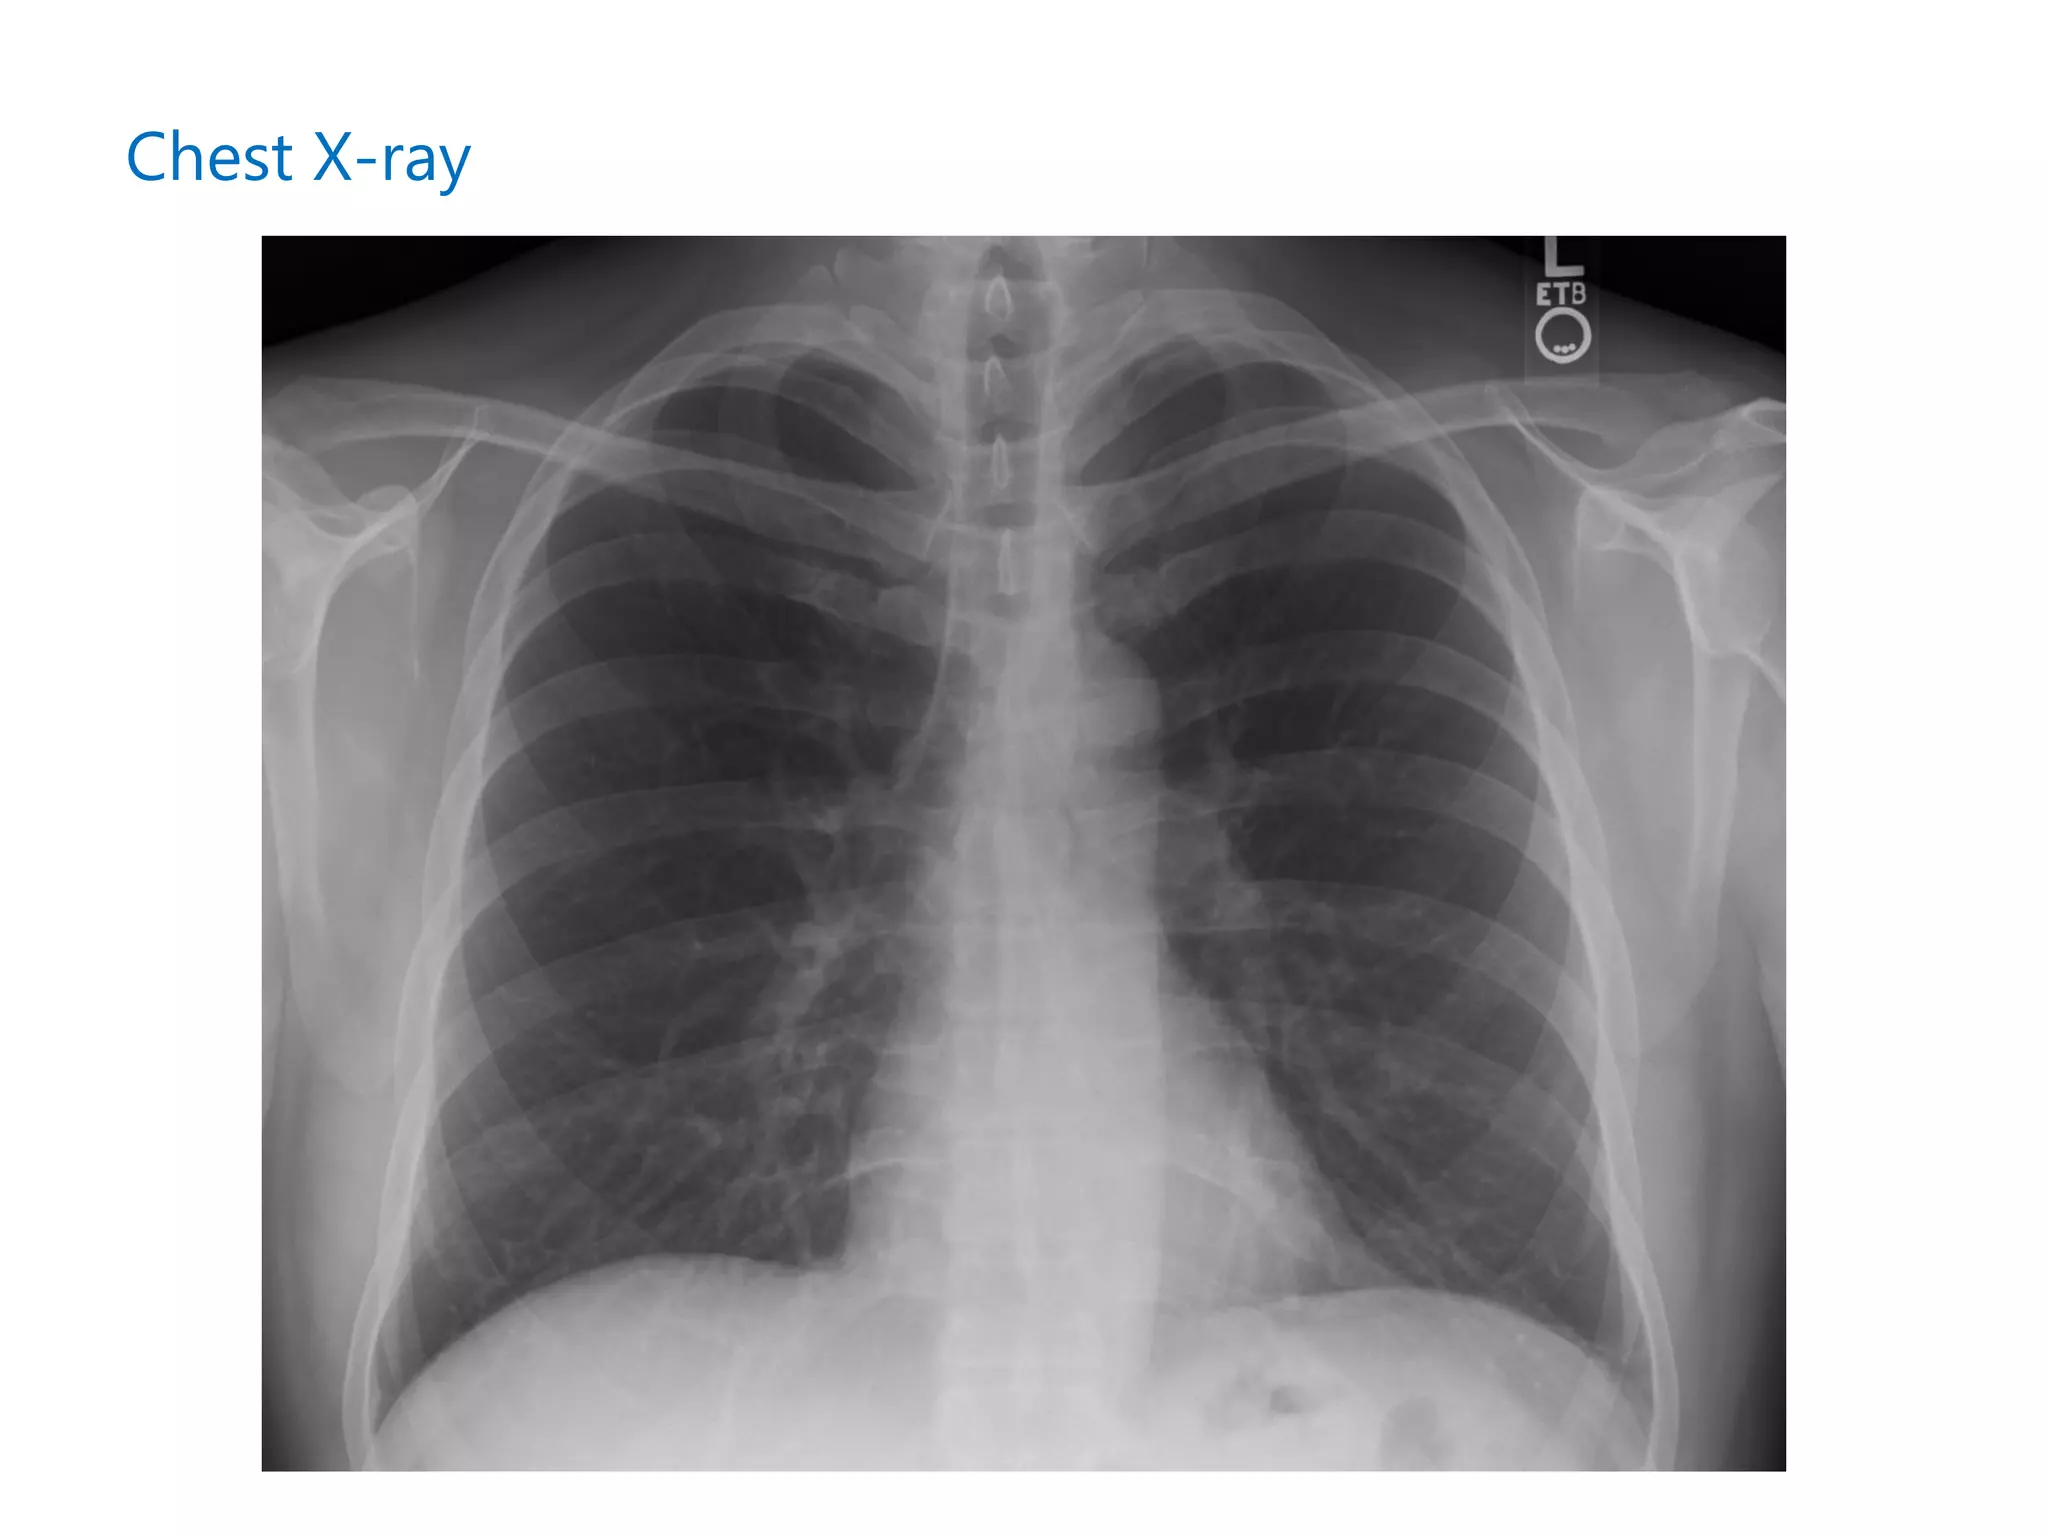

Chest X-ray